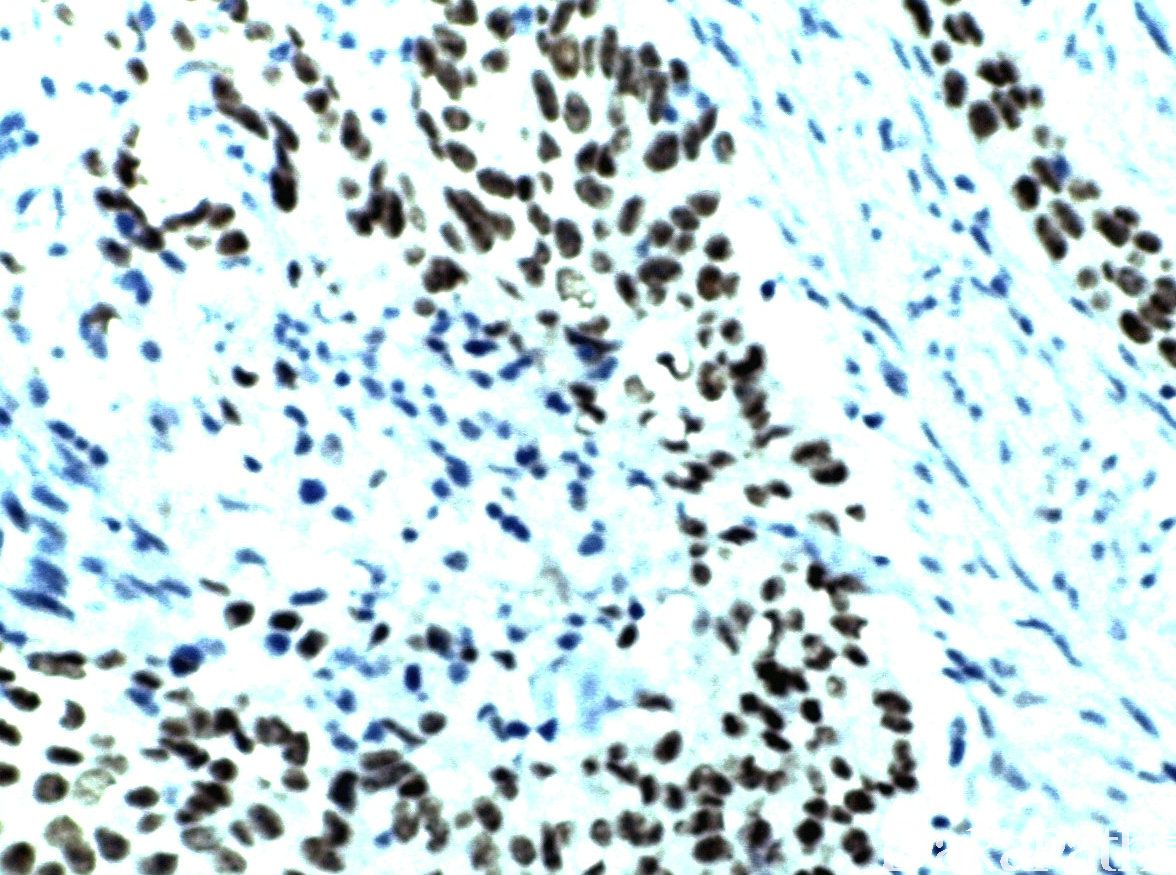

p63 蛋白亚型之一。在肺癌中,P40 敏感性与 P63 相当,但特异性优于 P63,在肺腺癌中几乎不表达。

信号定位: 胞核

鉴别肺腺癌(-)与鳞癌(+),特异性比 P63 更高。